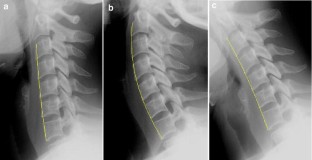

This study was conducted to evaluate a new method used to calculate vertebra orientation in medical x-ray images. The goal of this work is to develop an x-ray image segmentation approach used to identify the location and the orientation of the cervical vertebrae in medical images. We propose a method for localization of vertebrae by extracting the anterior—left—faces of vertebra contours. This approach is based on automatic corner points of interest detection. For this task, we use the Harris corner detector. The final goal is to determine vertebral motion induced by their movement between two or several positions. The proposed system proceeds in several phases as follows: (a) image acquisition, (b) corner detection, (c) extracting of the corners belonging to vertebra left sides, (d) global estimation of the spine curvature, and (e) anterior face vertebra detection.

Fig 3